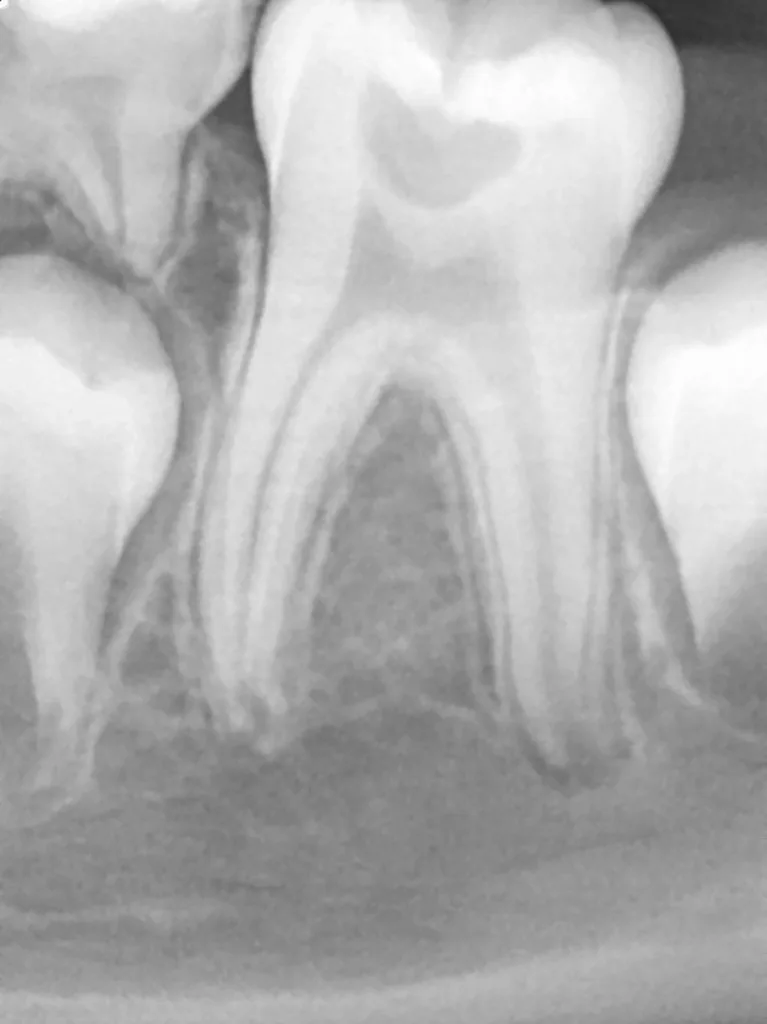

Bei routinemäßigen Röntgenkontrollen ergeben sich manchmal Zufallsbefunde unklarer Genese. So stellt sich beispielsweise bei der Betrachtung der Abbildung 1 die Frage, wie sich ein Zahnhartsubstanzdefekt so schnell entwickeln konnte. Ein weiteres Röntgenbild (Abb. 2), das vor dem Zahndurchbruch aufgenommen wurde, zeigt jedoch, dass es sich in diesem Fall nicht um Karies, sondern um die sogenannte präeruptive intrakoronale Resorption (PEIR) handelt. Für diesen Befund finden sich in der Fachliteratur auch noch andere Bezeichnungen wie „idiopathic external resorption of unerupted permanent teeth“ [1], „intra-follicular caries“ [2], „radiolucent lesions resembling caries“ [3], „occult caries“ [ 4] oder „pre-eruptive caries“ [5].

V. Slabkovskyi, O. Liutikovwährend des Durchbruchs des Zahnes 36.

Das fünfjährige Mädchen stellte sich 2017 zur jährlichen Routinekontrolle vor. Im Rahmen der Untersuchung wurden Röntgenaufnahmen der Milchmolaren gemacht (Abb. 2). Der klinische und radiologische Befund der vor uns früher gelegten Kompositfüllungen war gut, es wurde allerdings eine PEIR an den noch nicht durchgebrochenen ersten bleibenden Molaren festgestellt (Abb. 2). Den Eltern wurde empfohlen, sich unverzüglich bei Beginn des Durchbruchs der ersten Molaren erneut zur Behandlung vorzustellen. Ein Jahr später erschien die junge Patientin schmerzfrei zur Kontrolle. Der Zahn 36 war noch teilweise mit Gingiva bedeckt. Auf einer neuen Röntgenaufnahme (Abb. 1) wurde die PEIR-Läsion mit unveränderter Größe in pulpanahen Bereichen bestätigt (Grad 3 der Läsion nach Seow). Der Zahnschmelz sah intakt aus, es konnte kein pathologischer periapikaler Befund bei den noch nicht ausgewachsenen Zahnwurzeln festgestellt werden. Daraufhin wurden die verschiedenen Behandlungsmöglichkeiten von Fissurenversiegelung bis Vitalerhaltung der Zahnpulpa mit den Eltern des Kindes besprochen.